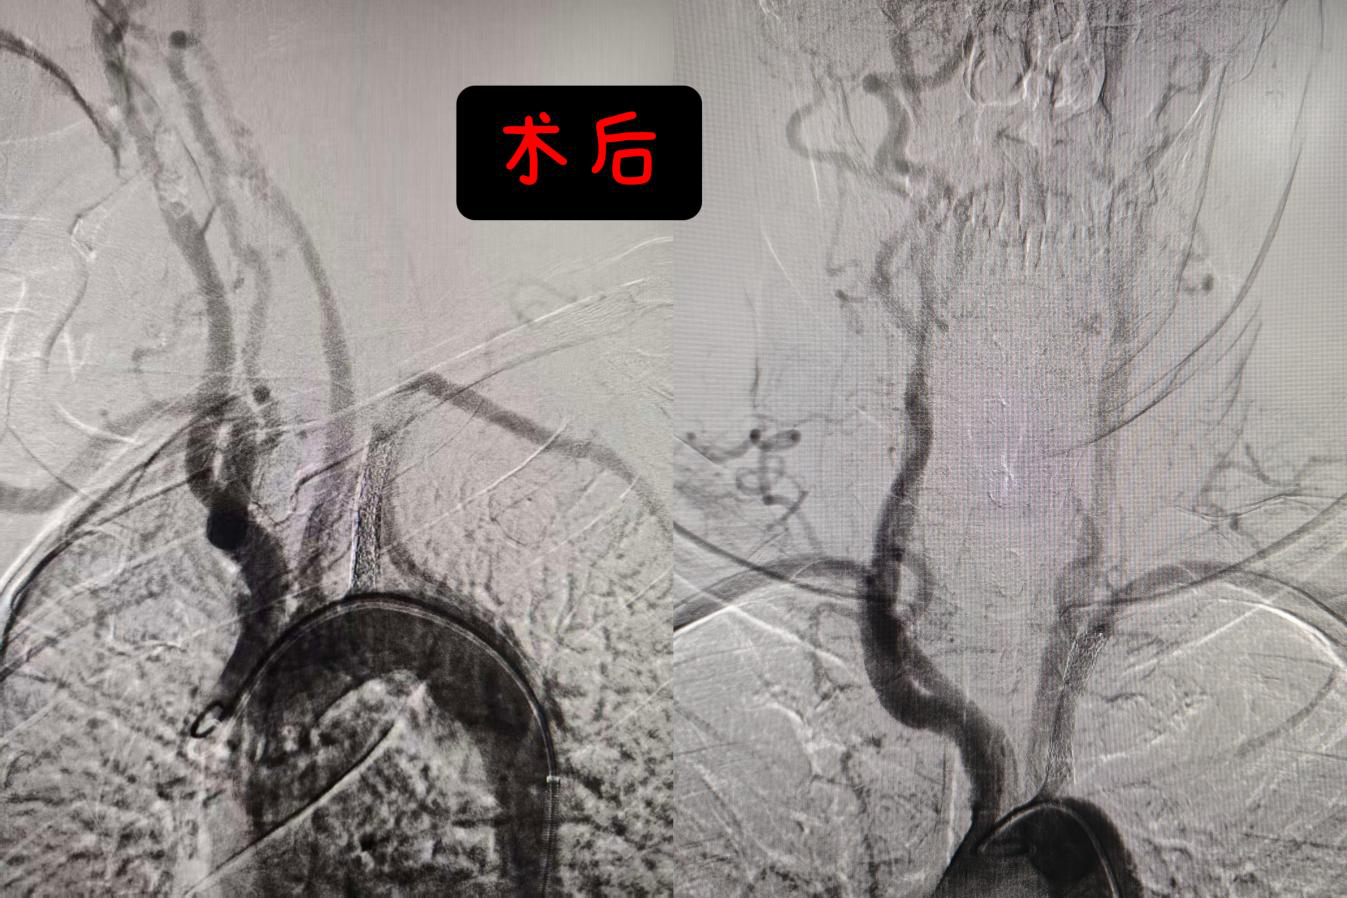

针对许大爷的病情,介入医学科团队为许大爷定制了最优方案-——“药涂球囊扩张+支架植入”。先用球囊扩张狭窄部位,再植入一枚药物涂层支架,将血管持久撑开,恢复正向血流;术中,医生仅通过其右侧大腿股动脉的一个穿刺小孔,送入细如发丝的导管与导丝,在血管造影的精准引导下,抵达闭塞的左锁骨下动脉;术后造影显示,原狭窄段血流通畅,左上肢血流立即改善。

术后许大爷最直观的感受是:“左手马上暖和了,好像一股暖流顺着手臂淌下来。”次日查房时,医生触摸其左腕,桡动脉已恢复有力搏动,双侧血压基本对称。